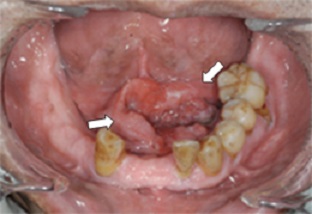

口底癌について

発現頻度はわが国では比較的少なく、口腔癌の約7%を占めます。

組織学的に中等度までの分化を示す扁平上皮癌が最も多いとされ、ついで腺癌、単純癌などがあり、口腔の他の部位よりも多様です。

早期に顎下リンパ節に転移しやすく、さらにオトガイ下あるいは深頸リンパ節にも転移し、しばしば反対側にも及びます。

症例

(社)日本口腔外科学会HPより引用